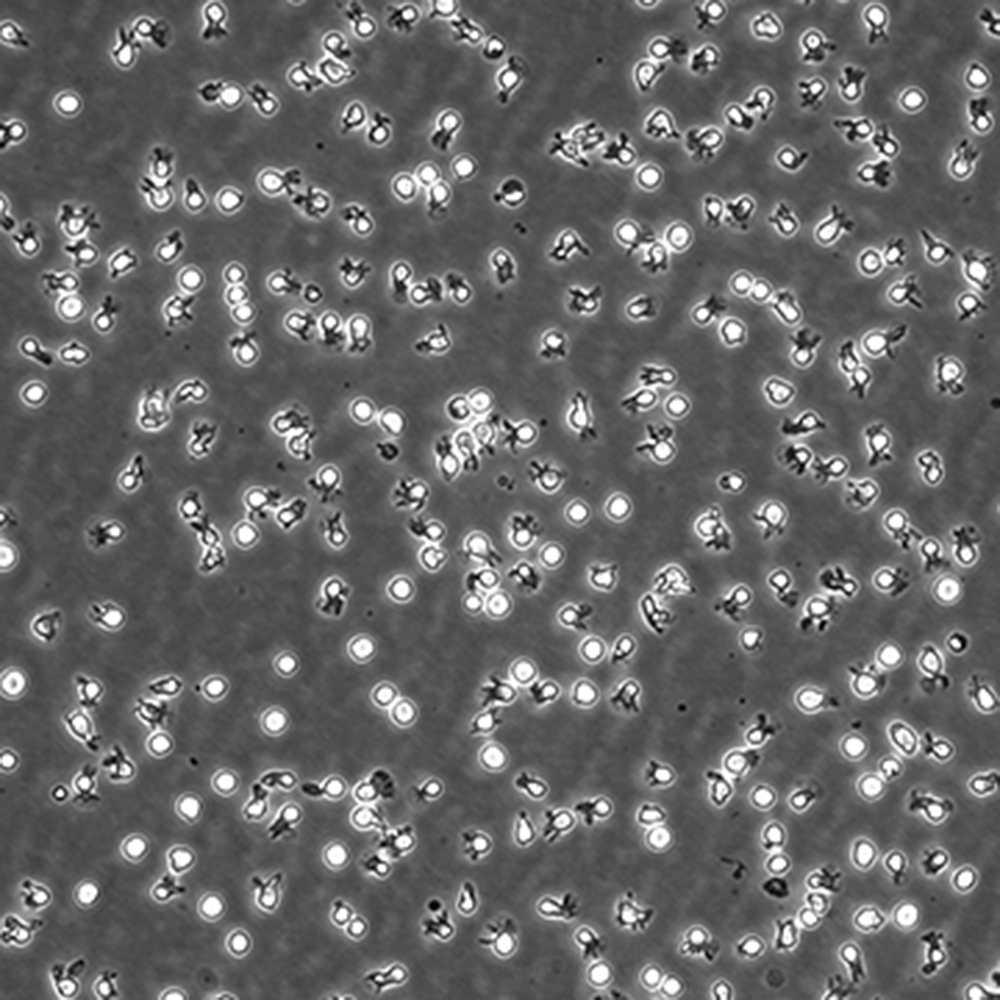

中文名稱 人彌漫大B細胞淋巴瘤細胞

組織來源 彌漫大B細胞淋巴瘤;男性

生長特性 懸浮

培養基 IMDM,90%;FBS,10%;雙抗。

培養條件 Atmosphere: Air, 95%; CO2, 5%。Temperature: 37℃